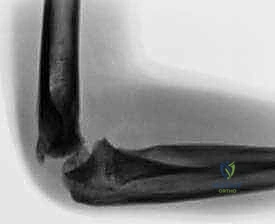

Clinical & Radiographic Imaging

Clinical Image